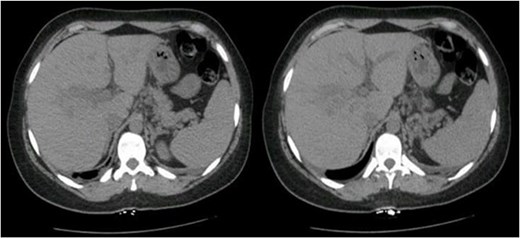

Postoperatively, her liver enzyme level continued to increase. Abdominal and pelvic computed tomography (CT) with IV contrast revealed multiple ill-defined, non-enhancing liver lesions, the largest measuring ~2.7 cm in segment VII, suggestive of hepatic infarction with mild periportal edema (Fig. 1). The liver appeared normal in size and shape with no focal lesions.

Abdominal and pelvic CT with IV contrast showed multiple scattered, ill-defined, and non-enhancing liver lesions, the largest measuring ~2.7 cm in segment VII.

Liver infarction presents with nonspecific signs, such as sudden upper abdominal pain, fever, jaundice, and elevated liver aminotransferases [12]. A liver biopsy helps to differentiate it from other conditions, and imaging tests are crucial for diagnosis. Abdominal CT is particularly useful in managing HELLP syndrome to rule out hepatic hematoma. In this case, liver infarction was attributed to HELLP syndrome [12]. Rupture usually occurs in the right hepatic lobe, causing right upper abdominal pain radiating to the back, shoulder discomfort, anemia, and low blood pressure [12].